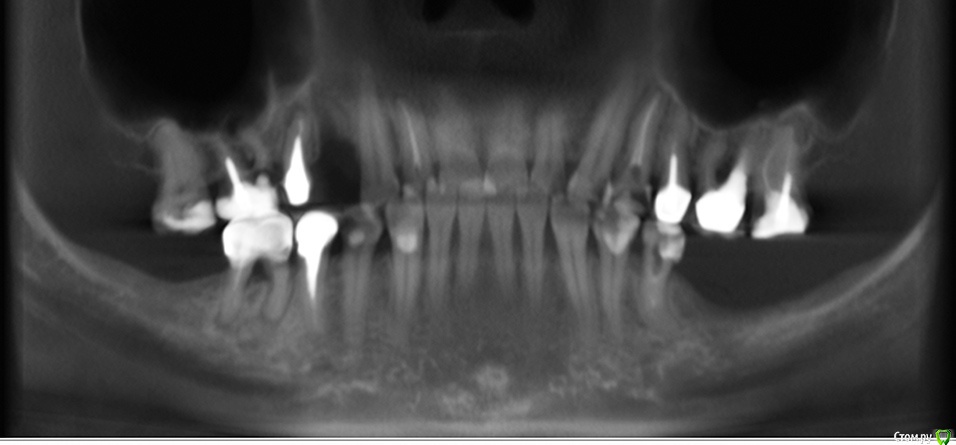

Clearr Опубликовано 12 июля, 2015 Автор Поделиться Опубликовано 12 июля, 2015 Эта проекция не предназначена для диагностики состояния зубовА на этой? Ссылка на комментарий

Bier Опубликовано 15 июля, 2015 Поделиться Опубликовано 15 июля, 2015 есть "киста" 100% 1 Ссылка на комментарий